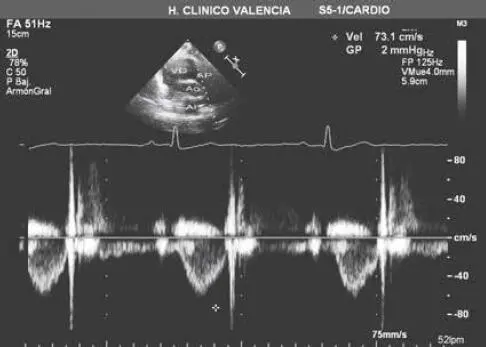

Fig 28 Registro de la velocidad del flujo sanguíneo obtenido mediante la - фото 22

Fig. 2.8 Registro de la velocidad del flujo sanguíneo obtenido mediante la técnica de Doppler continuo al dirigir el haz de ultrasonidos hacia la válvula aórtica tras situar el transductor en la posición apical. Abreviaturas: AI = aurícula izquierda; Ao = aorta; VD = ventrículo derecho; VI = ventrículo izquierdo.